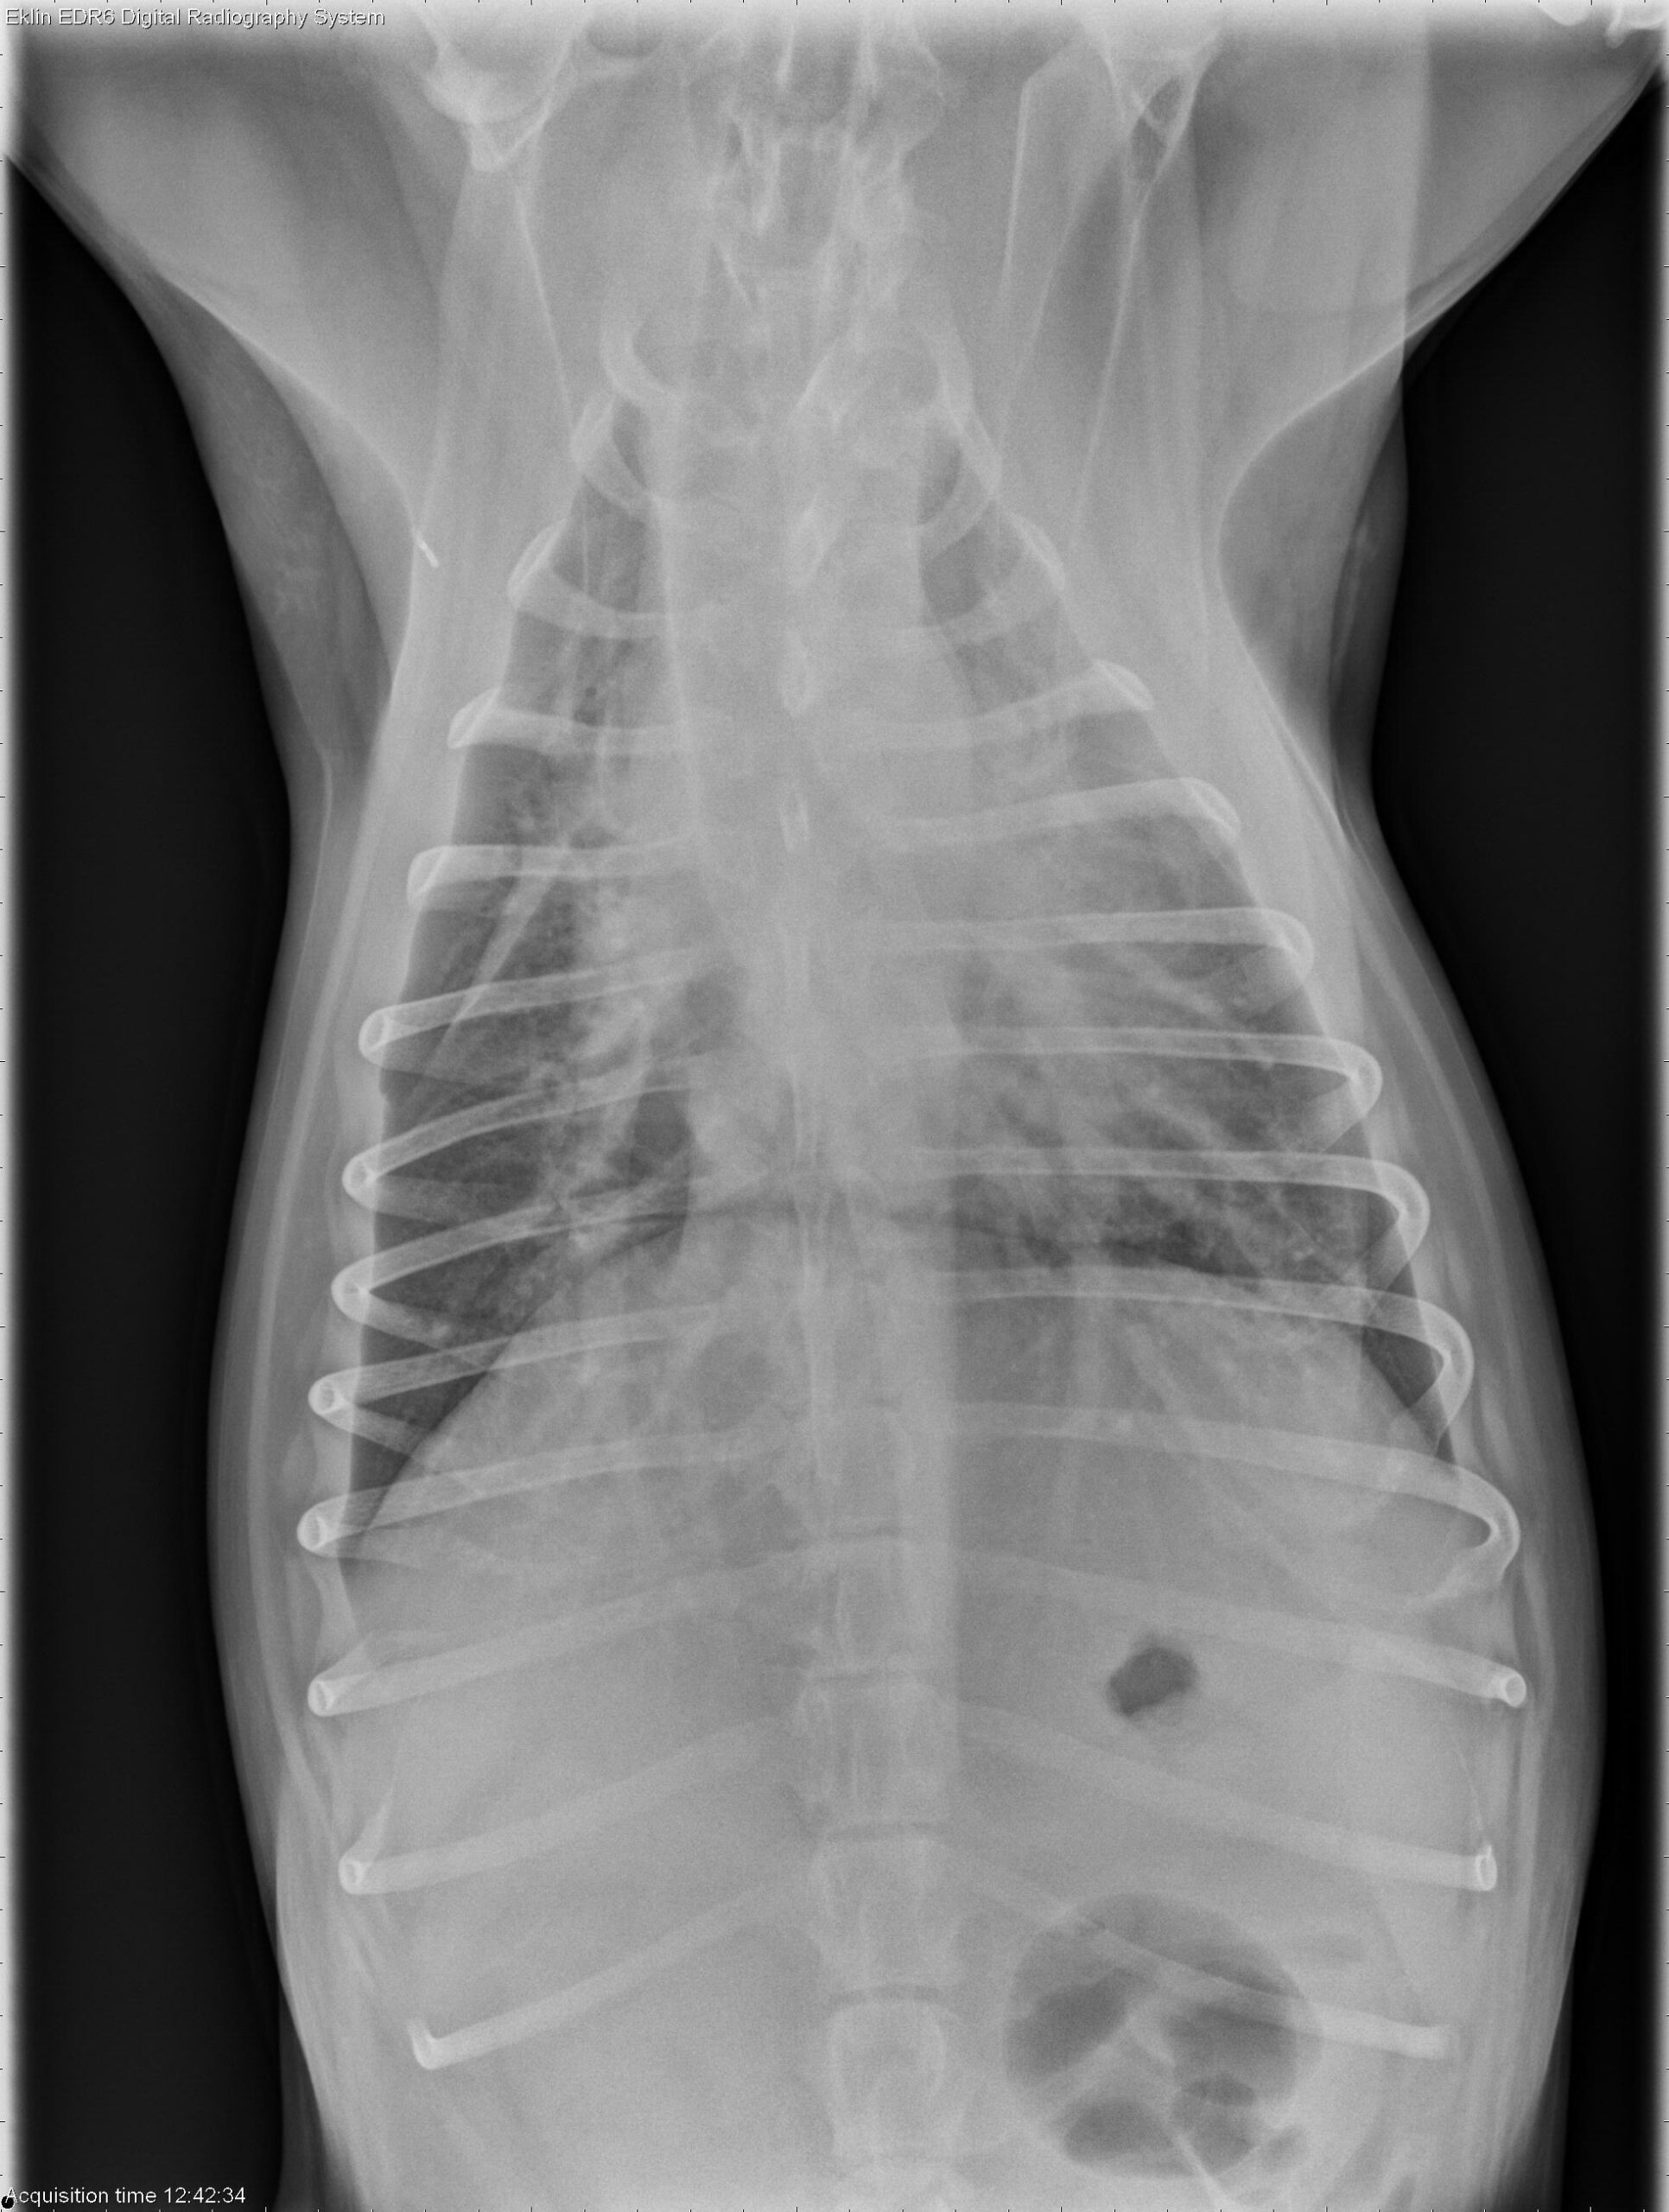

A 4-year-old spayed female Labrador Retriever is presented with fever of unknown origin (FUO).

Thorax: There is increased soft tissue opacity within the pleural space, with retraction of the lung lobes and partial silhouetting with the cardiac silhouette, consistent with pleural effusion. A patchy broncho-interstitial pattern is present in the lungs. The cardiovascular structures appear normal.

Abdomen: The abdomen is distended with poor peritoneal detail. The liver and spleen are enlarged with rounded margins. The colon is moderately distended with gas. The small intestines appear normal. The urinary tract is poorly visualized.

Bicavitary effusion may result from round cell neoplasia, metabolic disorders, or inflammatory diseases. The hepatosplenomegaly is most suggestive of lymphoma. Differential diagnoses for the pulmonary pattern include lymphoma and non-cardiogenic pulmonary edema.